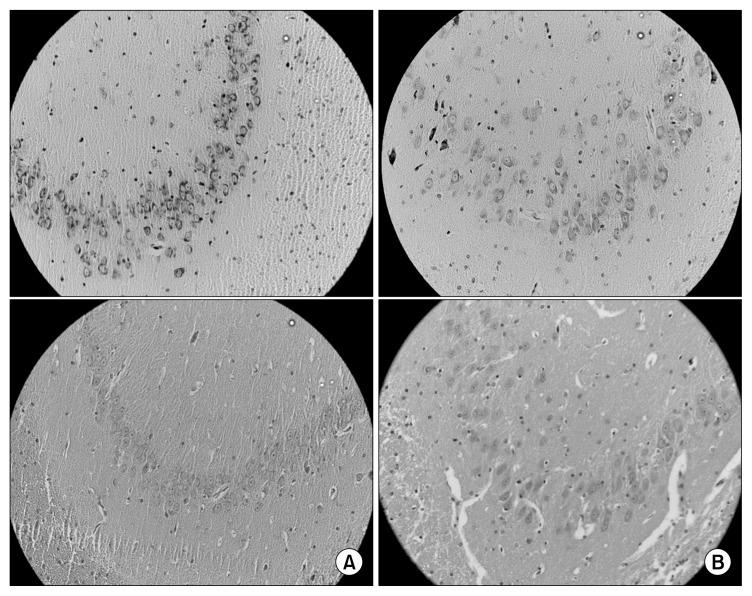

Diets rich in fruits and vegetables can prevent age-related diseases. This research was conducted to evaluate the effects of raisin consumption on the spatial memory and morphometric parameters of brain tissue in aging rats. Old rats (20 months of age) were divided into 2 groups: control and raisin, with 6 rats in each group. The raisin group received 6 g of raisins daily in addition to their food and water for 90 days. After treatments, all animals were evaluated by behavioral tests to assess spatial memory and learning alongside other tests including the ferric reducing antioxidant power (FRAP), malondialdehyde, and histological examinations. The results showed that there are significant differences in the Morris water task and passive avoidance learning of behavioral tests and biochemical tests (FRAP and thiobarbituric acid reactive substances) between the two groups. The histological study indicated that the cell count of the hippocampus, the diameter of the lateral ventricle, and area of the corpus callosum in the raisin group changed in comparison with the control group but they were not significant. The results demonstrated that raisins significantly raise antioxidant levels in blood and promotes cognitive and motor performance in aging rats.

富含水果和蔬菜的饮食可以预防与年龄相关的疾病。本研究旨在评估食用葡萄干对衰老大鼠脑组织空间记忆和形态学参数的影响。将老年大鼠(20月龄)分为2组:对照组和葡萄干组,每组6只大鼠。葡萄干组除食物和水外,每天给予6克葡萄干,持续90天。处理后,通过行为测试对所有动物进行评估,以评估空间记忆和学习能力,同时进行其他测试,包括铁还原抗氧化能力(FRAP)、丙二醛和组织学检查。结果表明,两组在行为测试(莫里斯水迷宫任务和被动回避学习)和生化测试(FRAP和硫代巴比妥酸反应物质)方面存在显著差异。组织学研究表明,葡萄干组海马体的细胞计数、侧脑室直径和胼胝体面积与对照组相比有所变化,但不显著。结果表明,葡萄干可显著提高衰老大鼠血液中的抗氧化水平,并促进其认知和运动能力。